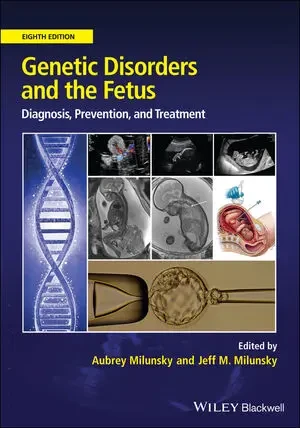

Books